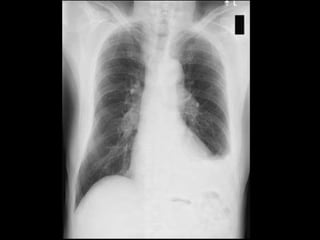

Left sided moderate pleural effusion infective in etiology,

probably tuberculosis involving the pleural space

 Chest X ray

Investigation  Baseline:  Completehemogram: RBC count, TC, DC, Hb, ESR  Urine routine  Mantoux test  Chest X ray  Diagnostic:  Diagnostic pleural tapping - gram staining, culture, AFB smear, cytology, pH, amylase level, glucose, LDH, SFAG